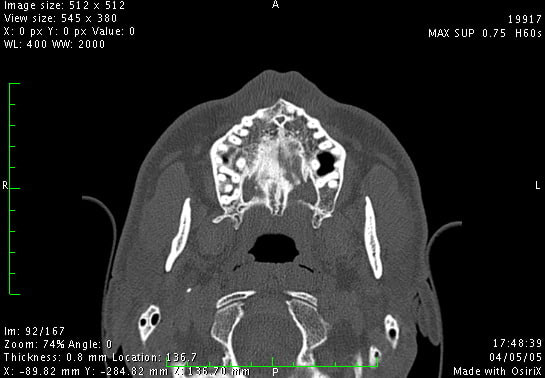

Je viens de revoir un jeune homme que j'ai dépanné en urgence cet été, suite à un problème infectieux récidivant sur sa 11.

De retour de vacances, son praticien a finalement extrait cette dent et l'a adressé à un stomato pour une éventuelle implantation, mais à la vue du scan (et selon mon patient) ce dernier n'est pas chaud pour une greffe. (proximité du canal palatin)

Voici quelques images, qu'en pensez-vous?

effectivement ton cas est typique des problemes rencontrés en zone anterieure.

les ecueils se situent a mon sens a plusieurs niveaux

1/ bien estimer la guerison osseuse au vu des antecedents infectieux cités me parait le plus important pour une bonne prise d'une greffe d'apposition- mieux vaut opérer 01 site "propre" a 3-06 mois q'un site douteux plus précoce.

une bonne decortication du site receveur et la fixation rigide du greffon sur un site qui saigne te donneront toutes les chances de succes.

2/ estimer la perte osseuse dans les 3 sens de l'espace- la greffe ne va pas forcément te redonner de la hauteur perdue ou des papilles...

3/ choix du site donneur

vu ta coupe reconstituée, tu auras surement plus d'os a la symphyse qu'au ramus mais la encore, le scan préop est hyper important pour estimer ton site donneur

4/ le canal naso palatin n'est pas un probleme du tout, Chicot a mille fois raisons,il te suffit de virer son contenu et le remplacer par un bio mat ou mieux de l'autogene et tu oublies les craintes infondées du stomato; dans ce canal pas grand chose d'inquiétant ou de dangereux et tu gagneras en vestibulolingual.